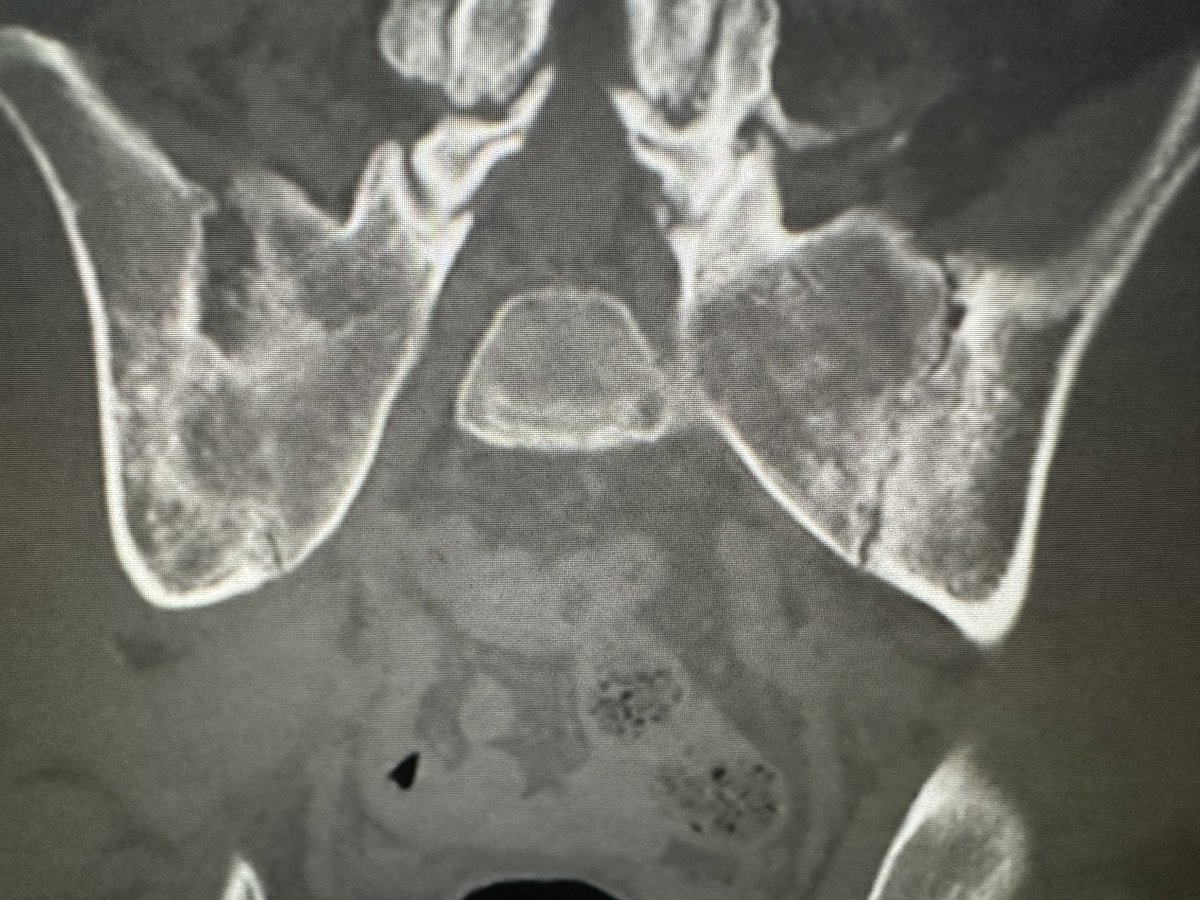

@mskteachingroom @mskradiologyuk @SidThakerMSK @jacja_ @veronica_giotas @PrimeFellowship Migrations of Ca tendinopathy

Spot Diagnosis?

The scapular ‘Y’ view is excellent for detection of coracoid fracture at the shoulder! [in this case not seen on AP internal / external rotation views]